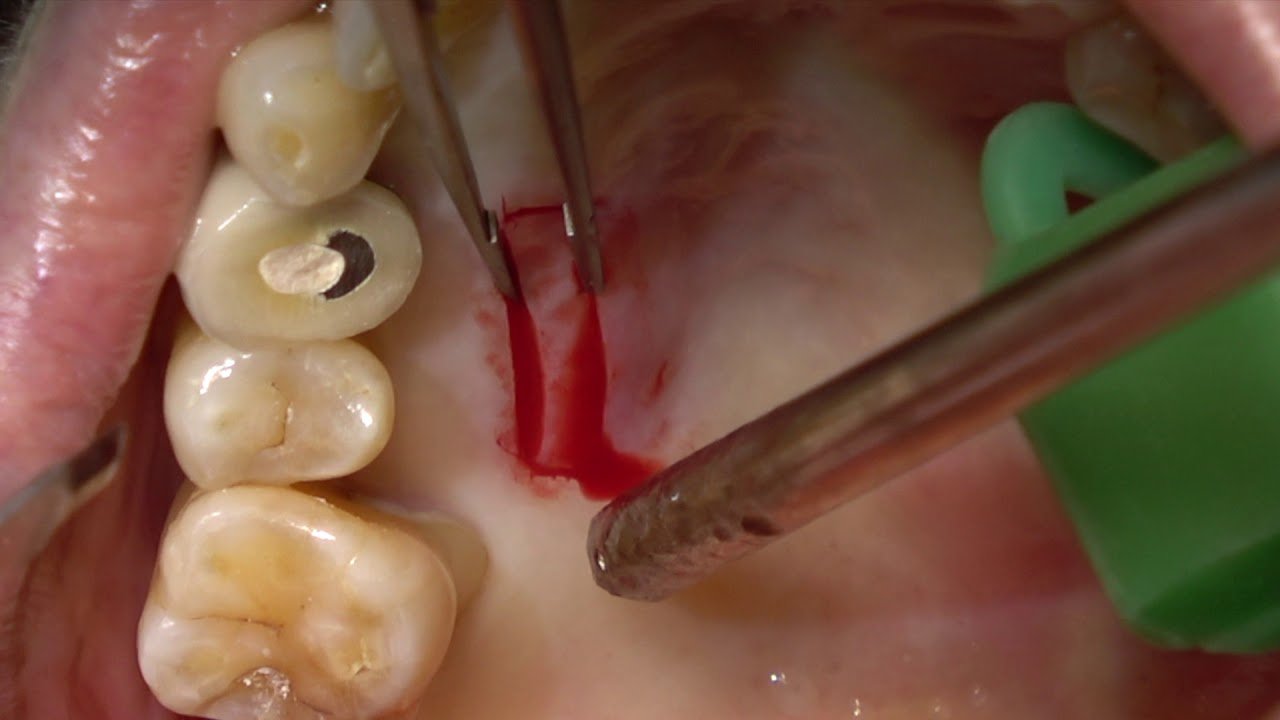

At AB Aesthetic and Dental Clinic, we perform this advanced microsurgical procedure with precision and care. The treatment involves taking a small layer of connective tissue — usually from the roof of the mouth — and placing it over the receded area to restore lost gum tissue and promote natural healing.